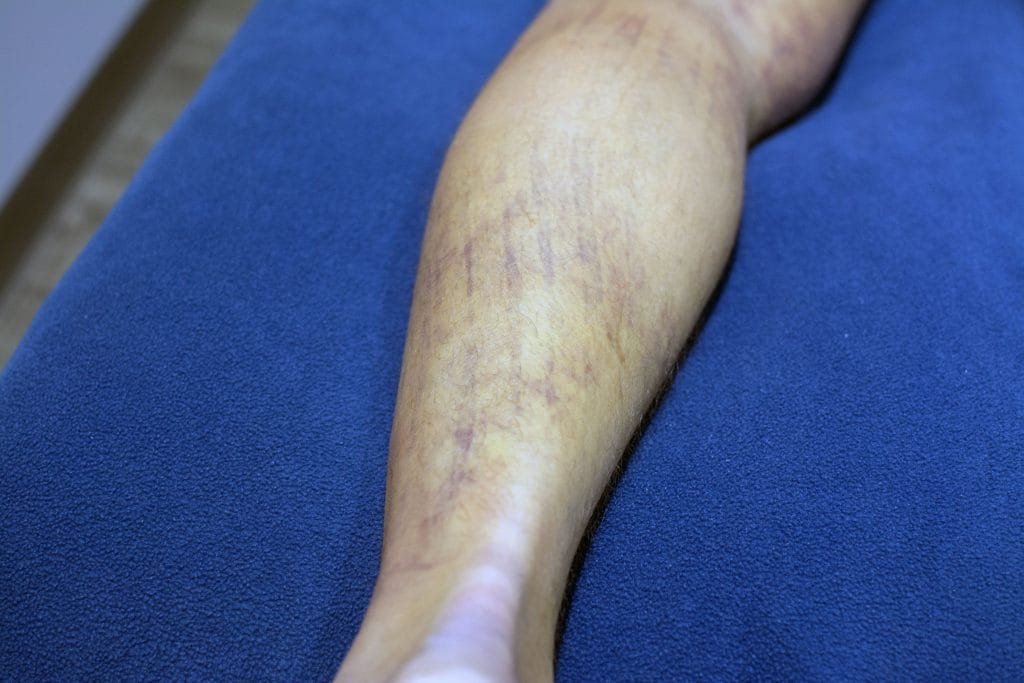

An MRI confirmed a hamstring rupture that would need surgery to repair. When a muscle is significantly torn or ruptured, it is common to see massive amounts of bruising as gravity pulls the blood down from the site of the muscle tear and pools it in the lower leg. I treated this patient with laser therapy and kinesiology taping to assist with pain and decrease the amount of bruising in his leg. 30 hours after the first treatment, he returned for a second session. Less visible discolouration was evident wherever I had put tape during his first visit. The intense pain the patient originally felt on the outside of his knee had now diminished, pain was primarily felt in the back of the thigh.

30 hours after applying Kinesiology Tape and two laser sessions.

With daily laser and Kinesiology Taping treatments for the next two days, the bruising and swelling in the patient’s leg significantly decreased. He was able to continue working (albeit not without significant discomfort) until he was able to have the rupture repaired surgically.